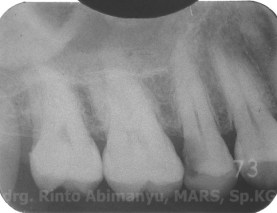

Kemudian diambil juga foto ronsen dari gigi itu, ini hasilnya..

Dari ronsen terlihat memang kavitas meluas sampai di bawah permukaan oklusal dan mengenai pulpa, tidak terlihat kelainan di periapeks.